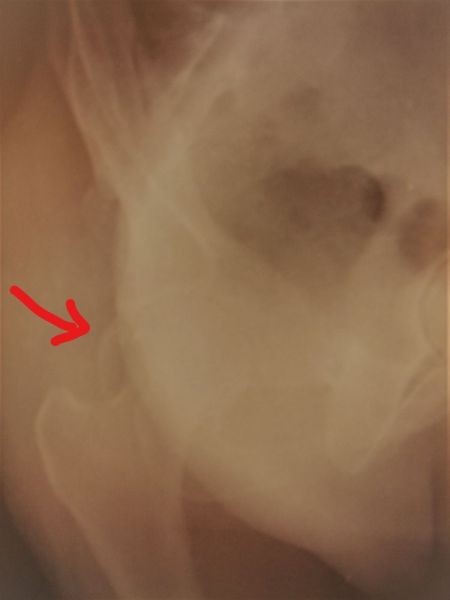

4. Posterior dislocation of the right hip with posterior acetabulum fracture in a 40-year-old male.

Treatment: 1st stage; closed reduction of the dislocation 2nd stage; open reduction of the acetabulum fracture with internal fixation

Ι. Obturator view of the right acetabulum shows the dislocation of the right hip II. Obturator x-ray right acetabulum shows the reduction of the hip, the red arrow shows the fracture III. Iliac x-ray acetabulum after the procedure shows the implant work (the patient referred to Mr. Antonios Papasotiriou who fixed the acetabulum)